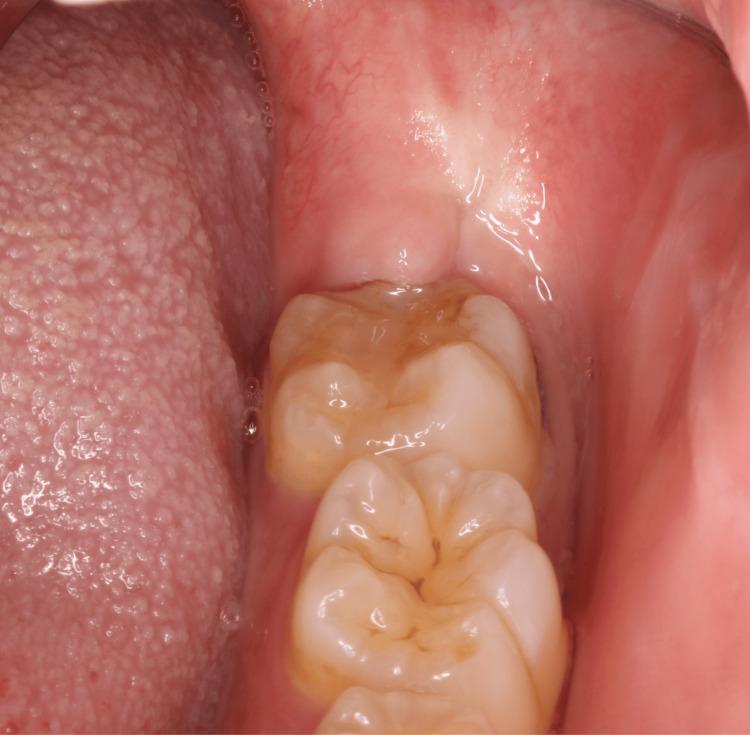

A 30-year-old pregnant woman developed an odontogenic cutaneous fistula (OCF) five months after having her wisdom tooth extracted. Initially diagnosed as a cutaneous furuncle, the condition was treated with amoxicillin, resulting in temporary improvement. However, it recurred after a month. Upon further evaluation, the lesion was diagnosed as an OCF originating from a chronic dental infection. Due to the patient's pregnancy, the treatment focused on non-invasive periodontal care, including scaling, while antibiotic therapy was maintained. Amoxicillin was initially prescribed; however, due to the progression of the infection, the treatment was switched to clarithromycin after consultation with a dermatologist. Over five months, the lesion gradually resolved, with no acute symptoms remaining. The pregnancy progressed without complications, and the patient gave birth to a healthy baby. This case underscores the challenges of managing odontogenic infections during pregnancy and highlights the importance of tailored antibiotic therapy to ensure the safety of both the mother and fetus.

一名30岁孕妇在拔除智齿五个月后出现牙源性皮肤瘘管(OCF)。最初被诊断为皮肤疖肿,使用阿莫西林治疗后病情暂时好转。然而,一个月后复发。进一步评估后,该病变被诊断为源自慢性牙齿感染的牙源性皮肤瘘管。由于患者怀孕,治疗重点为非侵入性牙周护理,包括洗牙,同时维持抗生素治疗。最初开具的是阿莫西林;然而,由于感染进展,经与皮肤科医生会诊后,治疗改为克拉霉素。五个多月来,病变逐渐消退,无急性症状残留。妊娠进展顺利,未出现并发症,患者生下一个健康的婴儿。该病例强调了孕期管理牙源性感染的挑战,并突出了定制抗生素治疗以确保母婴安全的重要性。